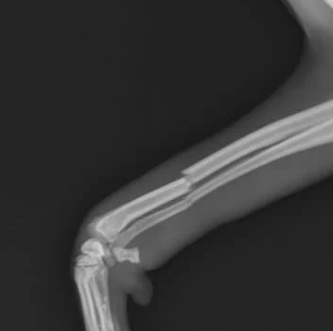

슬개골은 무릎뼈에 해당하는 부위로, 대퇴골과 경골 사이에서 관절이 정상적으로 움직이도록 돕는 역할을 합니다. 하지만 슬개골이 제자리에서 벗어나면 강아지슬개골 탈구가 발생하며,

슬개골 탈구는 1~4단계로 분류되며, 단계별로 보이는 강아지슬개골 탈구 증상이 다릅니다.

- 1기: 손으로 무릎을 만졌을 때만 탈구가 느껴짐, 평소 보행 정상

- 2기: 평소엔 괜찮지만 가끔 뒷다리를 들고 3발로 걷기

- 3기: 무릎뼈가 자주 탈구되어 절뚝거리며, 손으로만 제자리 복귀 가능

- 4기: 무릎뼈가 완전히 이탈, 손으로도 교정 불가, 정상 보행 불가능

3. 강아지슬개골 탈구 수술, 언제 필요할까?

수술은 보통 3기 이상에서 고려합니다.

이 단계에서는 뼈가 잦은 탈구로 제자리에 돌아가지 않거나, 연골 손상이 심각해 관절염 진행이 빠르기 때문이죠.